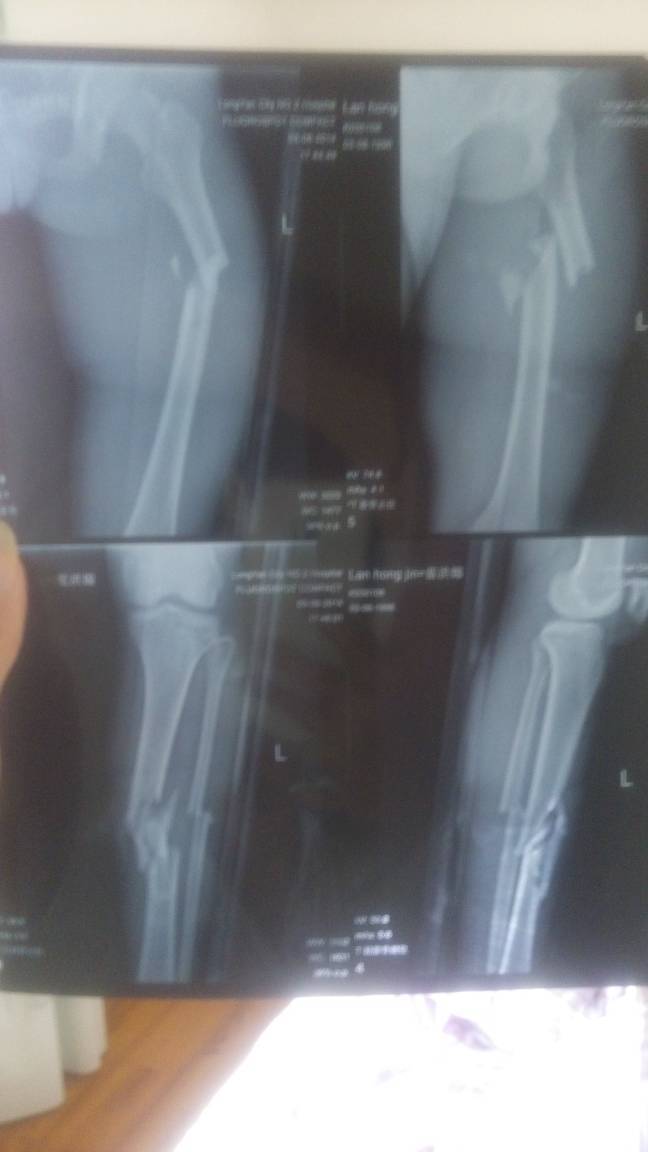

本人胫腓骨股骨开放性粉碎骨折,术后九个月,脱拐两个多月,请问现在可以剧烈运动吗?速跑,跳跃等 因为 本人胫腓骨股骨开放性粉碎骨折,术后九个月,脱拐两个多月,请问现在可以剧烈运动吗?速跑,跳跃等。因为有些事情很需要运动? 点击展开 匿名用户 2015-05-15 00:09 推荐回答 运动量大的尽量少去。你是粉碎性叨沙骨折!慢慢来,先做缓步宝悠运动生貌蛇,像慢跑类似的 匿名用户 2015-05-15 01:19 宝宝知道提示您:回答为网友贡献,仅供参考。 相关问题 左小腿胫腓骨开放性粉碎性骨折,手术一个月了 小腿开放性粉碎性骨折95天后能脱拐走路吗 大腿股骨折五个月,没有做剧烈运动钢板为何会折断?